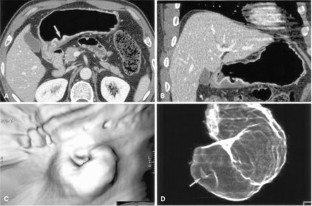

Figure 2